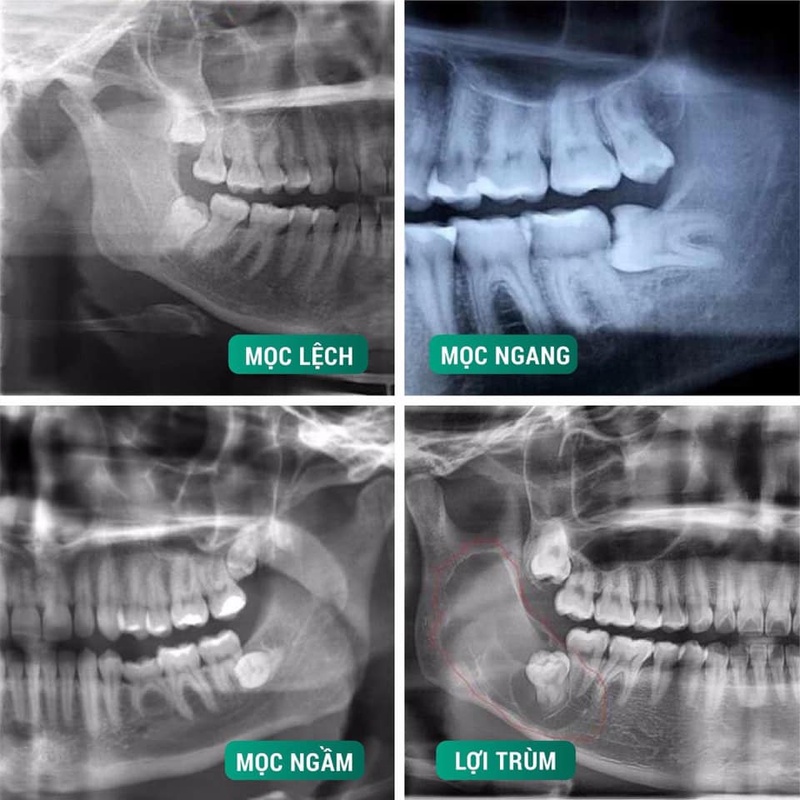

II. Các kiểu răng khôn mọc lệch phổ biến

Mức độ phức tạp của một ca tiểu phẫu phụ thuộc lớn vào hướng mọc của răng. Thông qua phim X- quang, bác sĩ sẽ xác định kiểu răng khôn mọc mà bệnh nhân đang gặp phải. Mỗi kiểu mọc sẽ có những nguy cơ tiềm ẩn khác nhau, cụ thể:

- Mọc lệch gần: Răng có xu hướng nghiêng về phía răng số 7. Đây là dạng răng khôn mọc lệch phổ biến nhất. Kiểu mọc này thường gây kẹt thức ăn và làm hư răng.

- Mọc lệch xa: Răng mọc nghiêng về phía sau cung hàm. Kiểu mọc này ít gặp hơn nhưng cũng gây khó khăn cho việc vệ sinh.

- Mọc ngang: Răng nằm ngang 900., song song với xương hàm và thường đâm trực tiếp vào chân răng số 7. Đây là trường hợp phức tạp, đòi hỏi bác sĩ có tay nghề cao.

- Mọc thẳng: Răng mọc theo phương thẳng đứng. Tuy nhiên, răng bị kẹt một phần hoặc toàn bộ dưới xương hàm do không đủ chỗ.